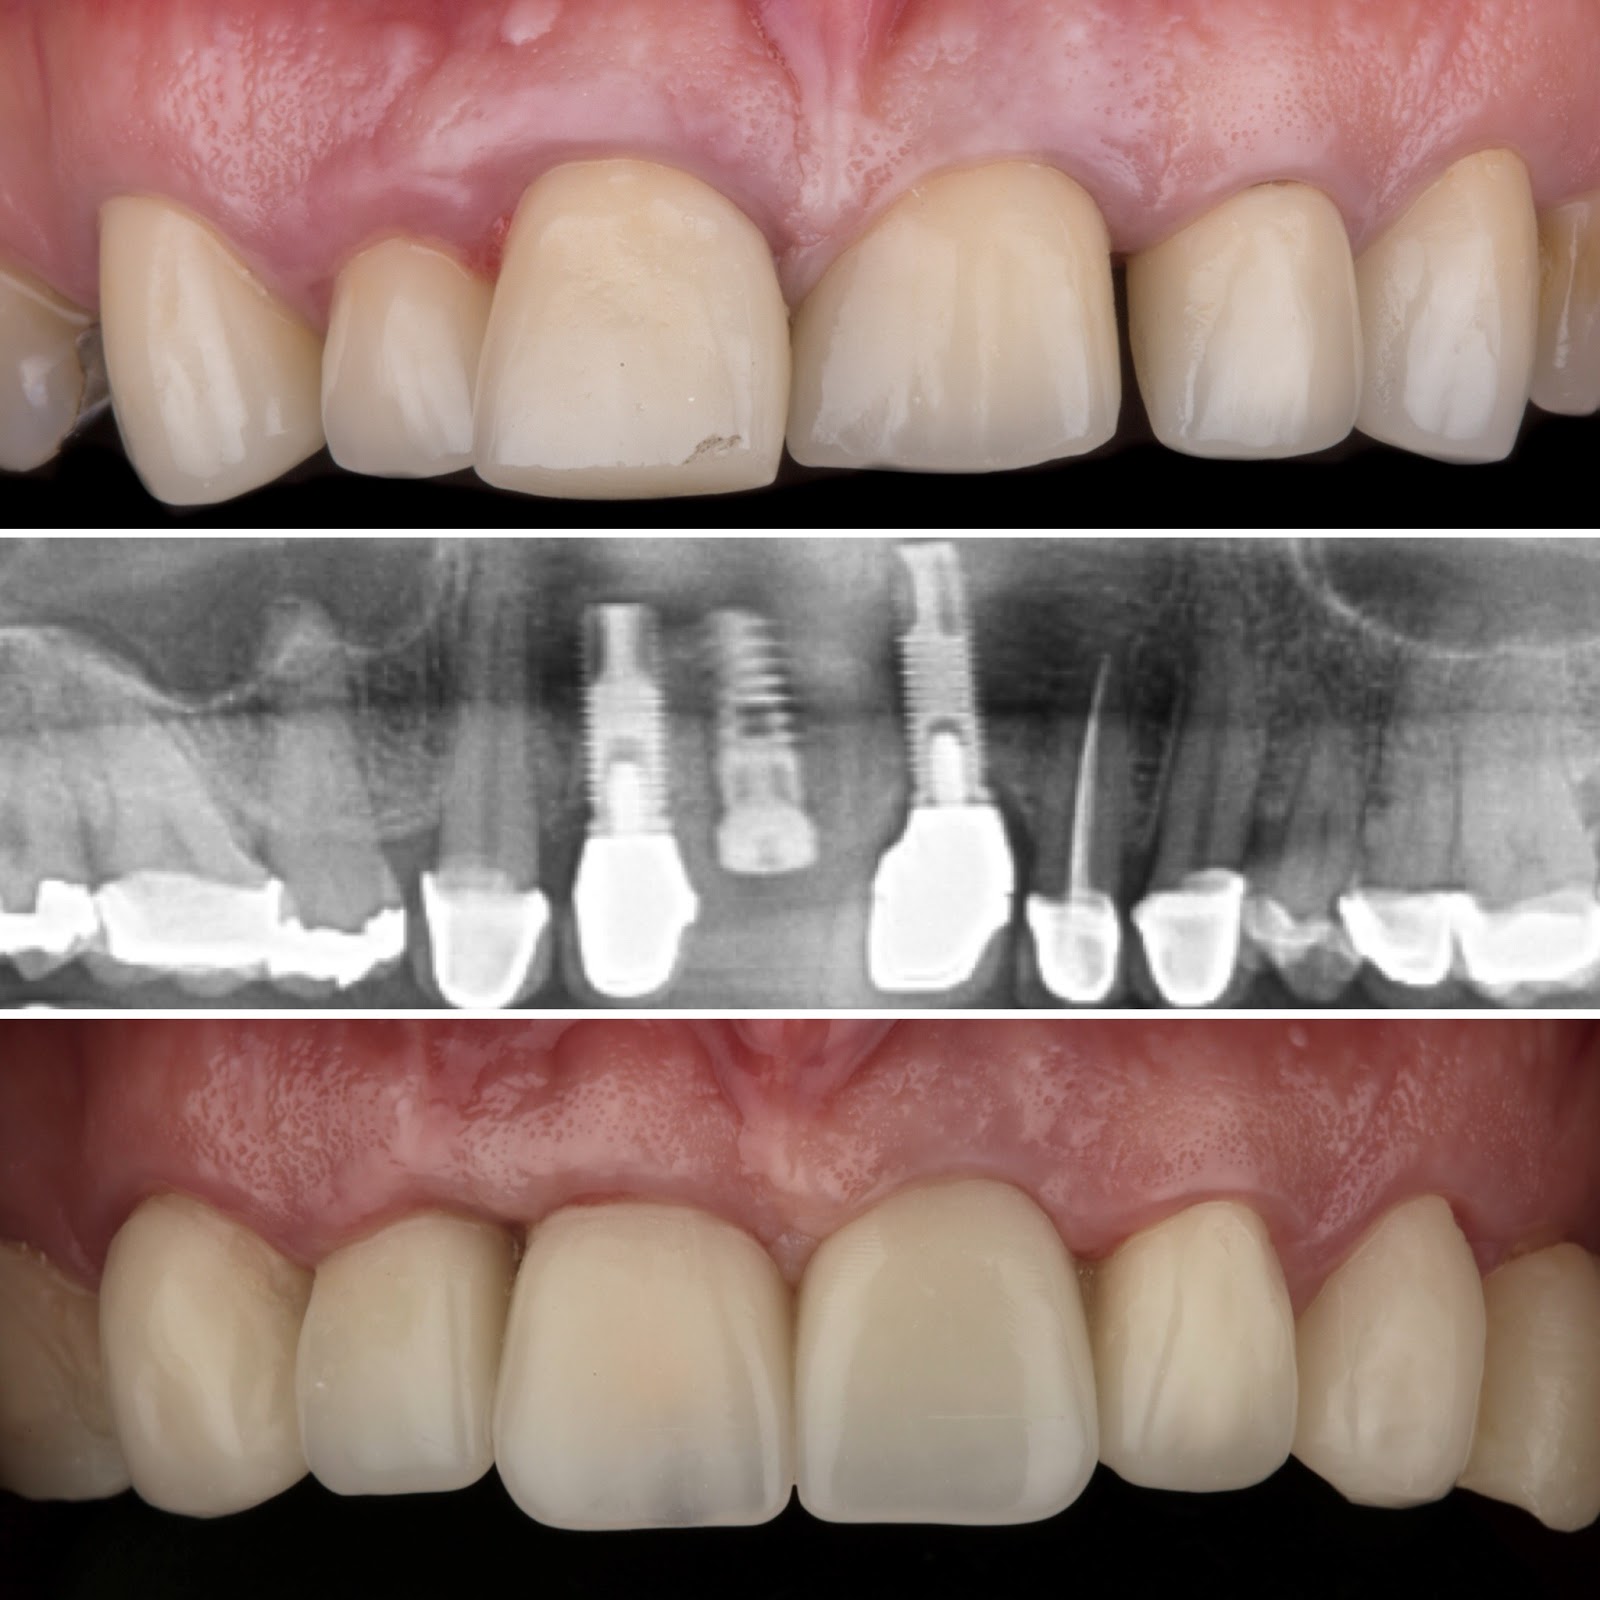

Dr. Ricardo Velázquez García es un dentista destacado en Colima, especializado en implantes dentales y cuidado integral de la salud bucal. Ubicado en el Centro Médico Puerta de Hierro, en Calle Ignacio Sandoval 1699-Consultorio 312, Girasoles, ofrece un ambiente profesional y acogedor para todos sus pacientes. Con una sólida reputación respaldada por una calificación de 5 estrellas basada en 235 opiniones, el Dr. Velázquez se distingue por su atención personalizada y la calidad de sus tratamientos. Sus pacientes valoran especialmente la amabilidad del equipo, la limpieza profunda y los resultados efectivos, como blanqueamientos dentales y procedimientos de bonding. La clínica cuenta con tecnología avanzada y un equipo comprometido en brindar una experiencia cómoda y segura. Para agendar una cita o solicitar información, puede comunicarse al teléfono 312 688 2357 o visitar su sitio web oficial https://dentaldesign.acecli.cloud/. El Dr. Ricardo Velázquez García es una opción confiable para quienes buscan mejorar su sonrisa y mantener una salud dental óptima en Colima.

Dr. Ricardo Velazquez García is a highly regarded dentist in Colima, specializing in dental implants and comprehensive oral health care. Located at Centro Medico Puerta de Hierro, Calle Ignacio Sandoval 1699-Consultorio 312, Girasoles, the clinic provides a professional and welcoming environment for all patients. With a 5-star Google rating from 235 reviews, Dr. Velazquez is known for his personalized approach and high-quality dental treatments. Patients appreciate the friendly and professional staff, thorough cleanings, and effective results including teeth whitening and bonding procedures. The clinic is equipped with advanced technology and a team dedicated to delivering a comfortable and safe experience. To schedule an appointment or request more information, contact the office at 312 688 2357 or visit the official website at https://dentaldesign.acecli.cloud/. Dr. Ricardo Velazquez García is a trusted choice for those seeking to improve their smile and maintain excellent dental health in Colima.